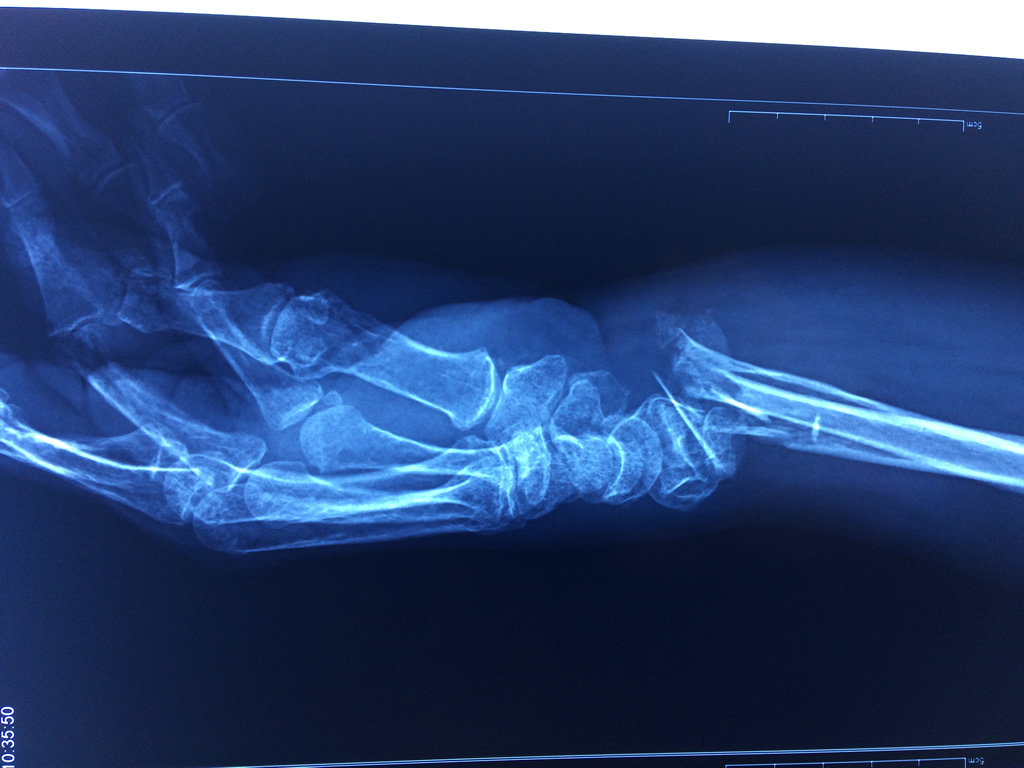

Calcaneo - Cirugías de Muñecas y Manos

Los procedimientos más comunes en cirugía de la mano son aquellos destinados a reparar traumatismos, incluyendo lesiones de tendones, nervios, vasos sanguíneos, y articulaciones; huesos fracturados; y quemaduras, cortes, y otros daños de la piel.